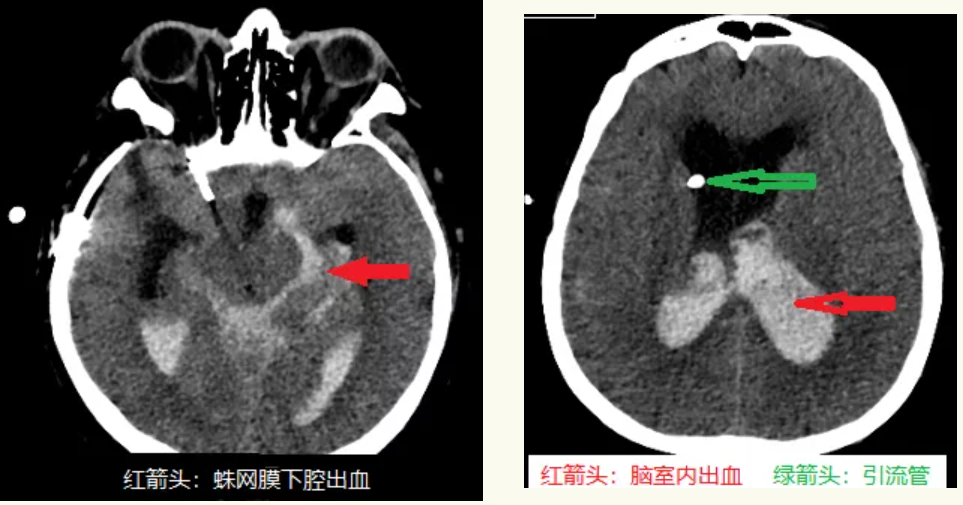

急诊行头CT显示:蛛网膜下腔出血、脑室系统内出血,脑室扩张,急诊科开通静脉通道,给予止血治疗,甘油果糖降低颅内压治疗,转运至神经外科时患者呼吸十分微弱,已经出现呼吸间停,血氧饱和度下降至84%,生命体征极不平稳,遂以“急性呼吸衰竭(中枢性)”急转至ICU。入院后给予镇静、止血、降低颅内压、控制血压、防止血管痉挛等对症治疗,病情稳定后神经外科副主任王宝庆带领主治医师郭知伟迅速为患者做了脑室外引流手术,梗阻性脑积水解决后,病人病情明显好转,逐渐恢复了部分意识。